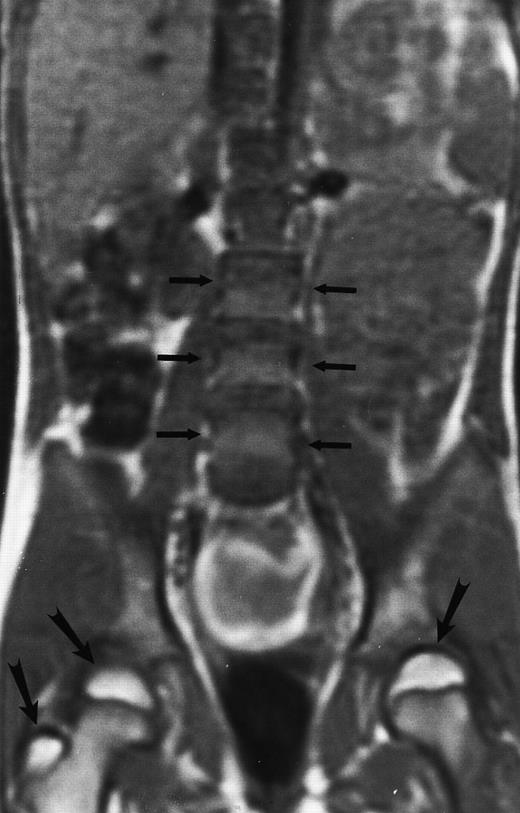

An 8-year-old boy with Burkitt's lymphoma and diffuse marrow involvement. Fat-suppressed, T2-weighted fast spin echo (3000/96, TR/TE) sagittal MR image of the lumbar spine shows heterogeneous signal intensity of the bone marrow and epidural extension of tumor (arrowheads) at the level of L5 and L2, with apparent preservation of the vertebral cortex.